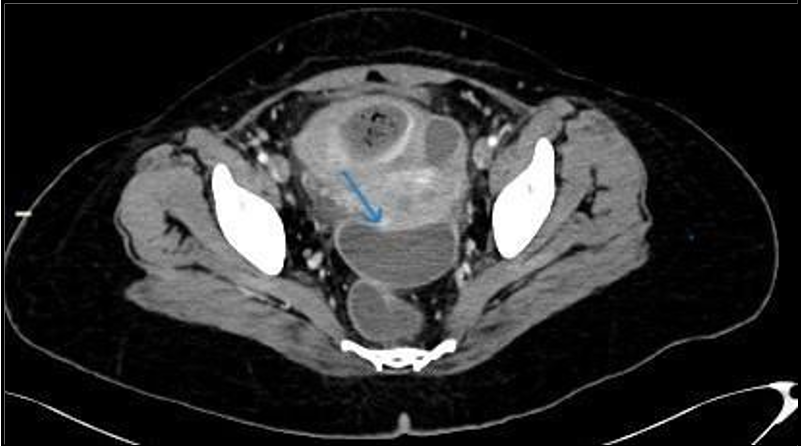

A CT scan of the abdomen and pelvis with contrast was performed to determine the cause of sepsis. It revealed a large, thick, enhancing walled-off area in the pelvis adjacent to the fundus of the uterus, containing multiple internal air locules with indistinct walls at places, and continuing air tracks. (Figure 1, 2). This represented an infected embolectomy-treated  subserosal  fibroid.  There  were  multiple intercommunicating pelvic infection collections in the cul-de-sac and vesico-uterine pouch (Figure 3). Diffuse peritonitis, omentomesenteric congestion, and edematous bowel loops were observed. Multiple prominent pelvic sidewall nodes were also noted. Therefore, rupture of pyomyoma with intraperitoneal spillage of infected content resulting in peritonitis is suggested.

Figure 3: Pelvic abscesses with larger in Cul de sac (arrow).